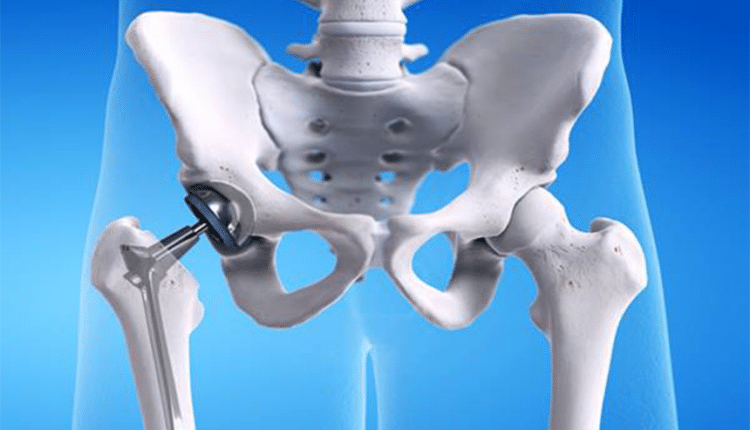

Kalça protezi ameliyatı, kalça eklemi sorunlarından kaynaklanan ağrı, kısıtlılık ve fonksiyon kaybının tedavisi için etkili bir çözümdür. Bu cerrahi müdahale, hastaların yaşam kalitesini artırmayı ve günlük aktivitelerine daha rahat katılmasını sağlamayı amaçlar. Ancak, her tıbbi müdahalede olduğu gibi, Kalça Protezi Ameliyatının da belirli riskleri ve avantajları vardır.

Ameliyatın güvenilirliği genellikle hasta seçimi, cerrahi teknik ve postoperatif bakıma bağlıdır. Kalça protezi ameliyatının genel olarak başarılı ve güvenilir bir prosedür olduğunu söylemek mümkündür. Modern cerrahi teknikler, ileri implant tasarımları ve cerrahi ekipmanların gelişimi sayesinde bu ameliyatın komplikasyon oranları düşmüştür.

Ancak, her cerrahi müdahalede olduğu gibi kalça protezi ameliyatı da bazı riskleri içerir. Enfeksiyon, kan pıhtıları, implantla ilgili sorunlar ve sinir hasarı gibi potansiyel komplikasyonlar ortaya çıkabilir. Hastanın genel sağlık durumu, yaş, obezite gibi faktörler bu riskleri etkileyebilir. Bu nedenle, ameliyat öncesi detaylı bir değerlendirme ve hasta ile paylaşılan bir karar süreci önemlidir.